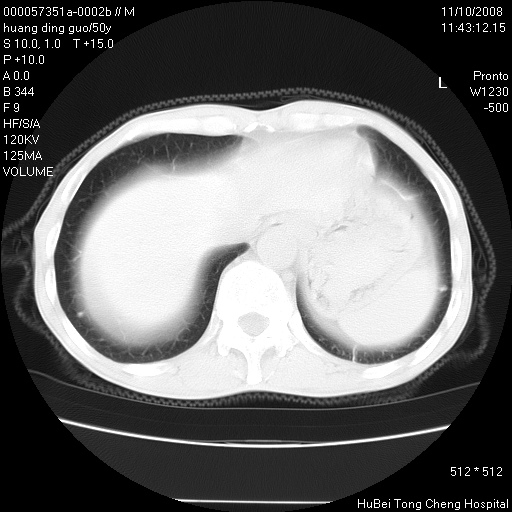

患者 男,50岁。左侧腰背部疼痛3月余,伴消瘦。平素健康,无传染病史。

胸部ct轴位平扫(层厚10mm,螺距1.5,重建间隔10mm),图像如下:

左肺下叶背段有一厚壁空洞,外壁呈锯齿状伴毛刺改变。空洞相邻胸膜有牵拉改变。左肺下叶血管支气管束不规则增粗,小叶间隔增厚。胸椎骨质破坏。考虑左肺下叶周围型肺癌伴左肺下叶癌性淋巴管炎、胸椎转移。

左肺下叶背段有一厚壁空洞,外壁呈锯齿状伴毛刺改变。空洞相邻胸膜有牵拉改变。左肺下叶血管支气管束不规则增粗,小叶间隔增厚。胸椎骨质破坏。考虑左肺下叶周围型肺癌伴阻塞性肺炎、胸椎转移。其他待排

左肺下叶背段有一厚壁空洞,内壁不规则,外壁呈锯齿状伴毛刺改变。空洞相邻胸膜有牵拉改变。周围呈絮状炎性改变,左肺下叶血管支气管束不规则增粗,小叶间隔增厚。胸椎骨质破坏。考虑左肺下叶周围型肺癌伴左肺下叶阻塞性肺炎、胸椎转移。